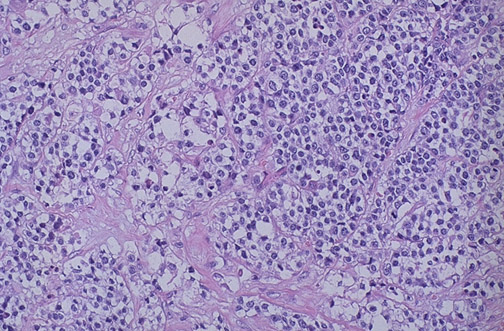

A rare neoplasm that appears most commonly in the first decade of life is the rhabdomyosarcoma. This malignant neoplasm has skeletal muscle derivation. The alveolar variant is shown here. These neoplasms occur most frequently in the head and neck area, as well as the genitourinary tract. |